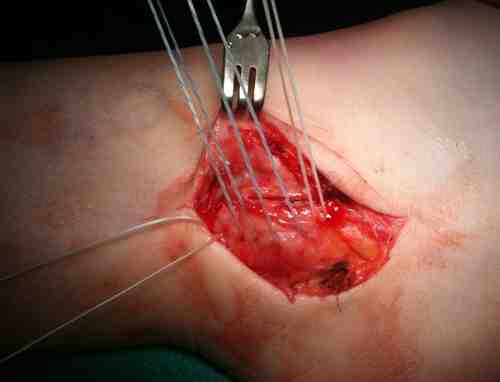

Direct repair of SPR +/- groove deepening

Technique

Groove deepening

- deepen with burr

- can elevate fibrocartilage base / deepen groove with burr / replace fibrocartilage base

Identify avulsion of SPR from fibula, assess groove, insert anchors in fibula

Repair + advancement / tightening of SPR with pants over vest technique